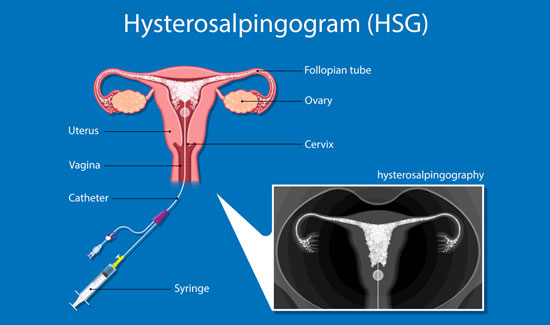

Hysterosalpingography